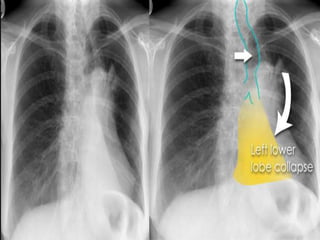

Left lower lobe collapse

 The tracheal deviation to left.

 classical appearance of a 'double left heart border,' or a

'sail sign' (orange). The second heart border (curved

arrow) is due to the dense edge of the collapsed left

lower lobe, which has been squashed into a triangle or

sail shape.

PA (right) and lateral (left) chest radiographs in a patient with tight left

lower lobe collapse. Note the triangular white opacity (black arrows)

behind the heart obscuring the posteromedial left hemidiaphragm.

Left lower lobe collapse.